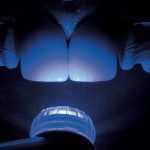

As imagens 18a, b, c e d apresentam o procedimento de moldagem com uma silicona de adição em etapa única. O material leve é injetado assim que o fio Pro-Retract 0000 é removido com o uso de uma pinça (figura 18a). O material leve, depois de injetado em todas as cervicais dentais, é aplicado um jato de ar para impelir o material contra os dentes (figura 18b); logo a seguir, é levada a moldeira em posição com o material pesado (Putty) (figura 18c). A vista final da moldagem, na qual se pode ver nitidamente que o material leve copiou adequadamente a região cervical dos dentes pode ser apreciada na figura 18d.

- Figura 18a

- Figura 18b

- Figura 18c

- Figura 18d